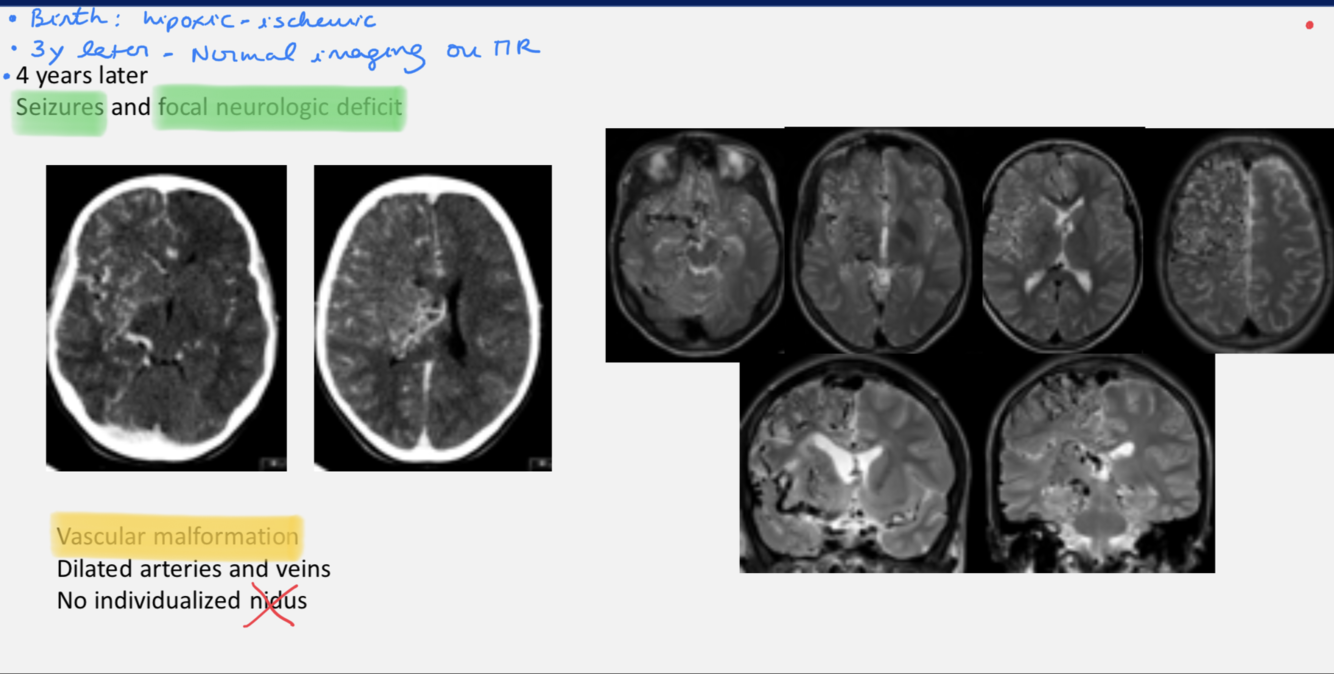

AVM - ddx

.